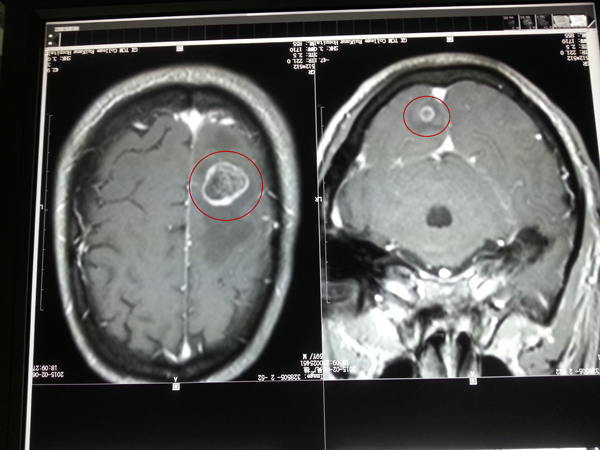

磁共振右顶叶肿瘤2厘米,左小脑瘤1.2厘米